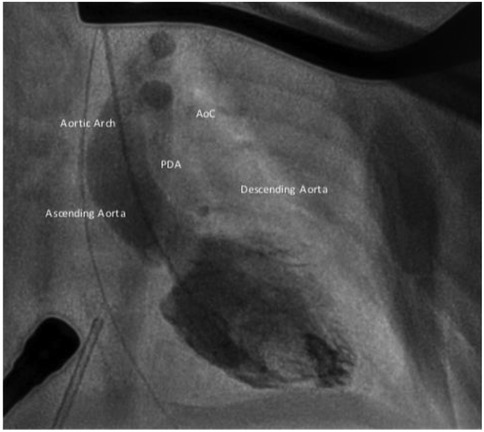

The first balloon angioplasty for AoC was performed in 1982, by J. Lock (35). BA effectively reduces the pressure gradient in the short- to mid-term follow up. In cases of native AoC, it may be considered for extremely low-birth-weight infants or patients in cardiogenic shock as a bridge to surgery (36, 37) (Figure 2). However, several studies have indicated a higher risk of aneurysm formation and restenosis with isolated BA compared to surgery (4). Therefore, surgery remains the favored treatment for infants, while BA is often the first choice for managing recurrent AoC after surgical repair.

Both the AHA/ACC and ESC Guidelines recommend percutaneous stent implantation as the first-line treatment for adolescents and adults with AoC (4, 38, 39) (Figure 3). Several studies have demonstrated the high effectiveness of stenting, with lower morbidity and mortality rate compared to surgery. Unlike balloon angioplasty, stenting carries a minimal risk of aortic aneurysm and dissection (4, 40, 41).